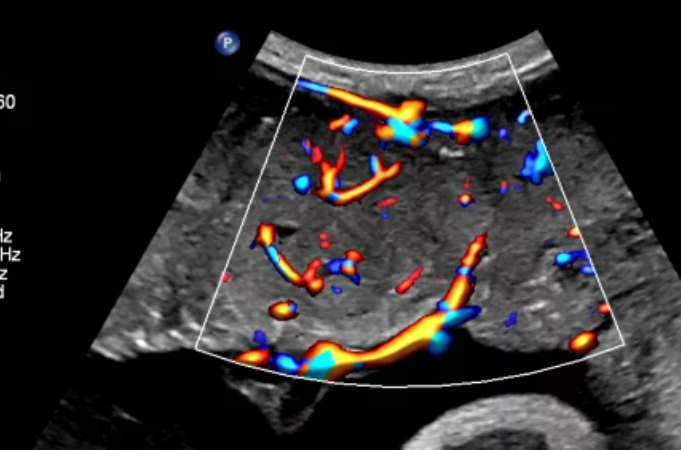

MicroFlow Imaging – мелкие сосуды в высоком разрешении

Специальная технология позволяет четко отображать на экране и снимках участки тканей с медленным или слабым кровотоком. Это очень ценно при исследованиях сосудов.

Благодаря использованию технологии специалисты получают:

- улучшенную визуализацию просветов;

- высокое разрешение в 2D и отличное качество получаемого изображения;

- минимальное количество артефактов при исследовании некрупных сосудов.

CPA дуги аорты плода с Flow Viewer

ЦДК сердца плода, четыре камеры, с Flow Viewer

CPA плаценты с Flow Viewer

ЦДК перфузии яичника с Flow Viewer с датчиком C10-3v

MFI яичника, Flow Viewer

Кровоток в яичнике с MFI и датчиком C10-3v

ЦДК перфузии легких плода с Flow Viewer